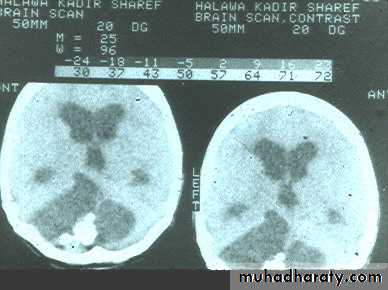

Hydrocephalous

2 types

Obstructive ( non – communicating )

Non –obstructive ( communicating )

No obstruction of the ventricular pathway , but the absorption of the csf at the level of arachnoids' granulation is occluded secondary to lodge by blood clot or inflammatory cell or infection post meningitis most commonly to occur post SAH .

CT Scane